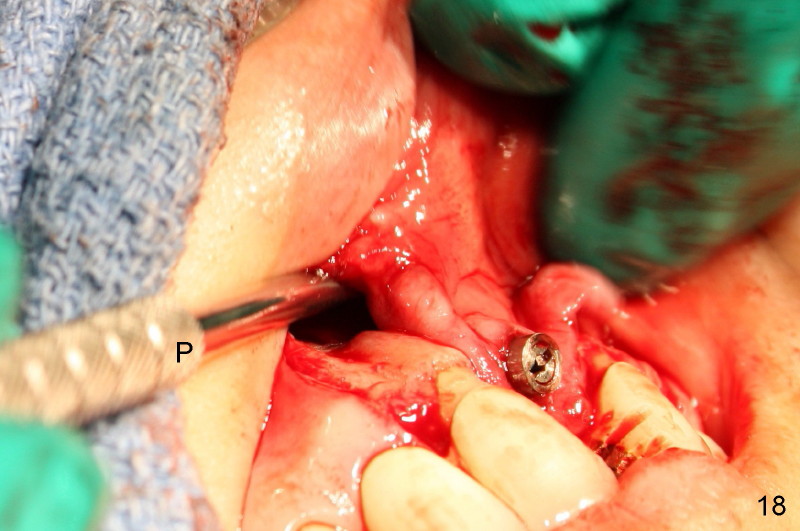

Segmental Osteotomy for Misplaced Implant

This corrective surgery was performed by Dr. Bernee Dunson.

Xin Wei, DDS, PhD, MS 1st edition 12/21/2011, last revision 12/23/2011